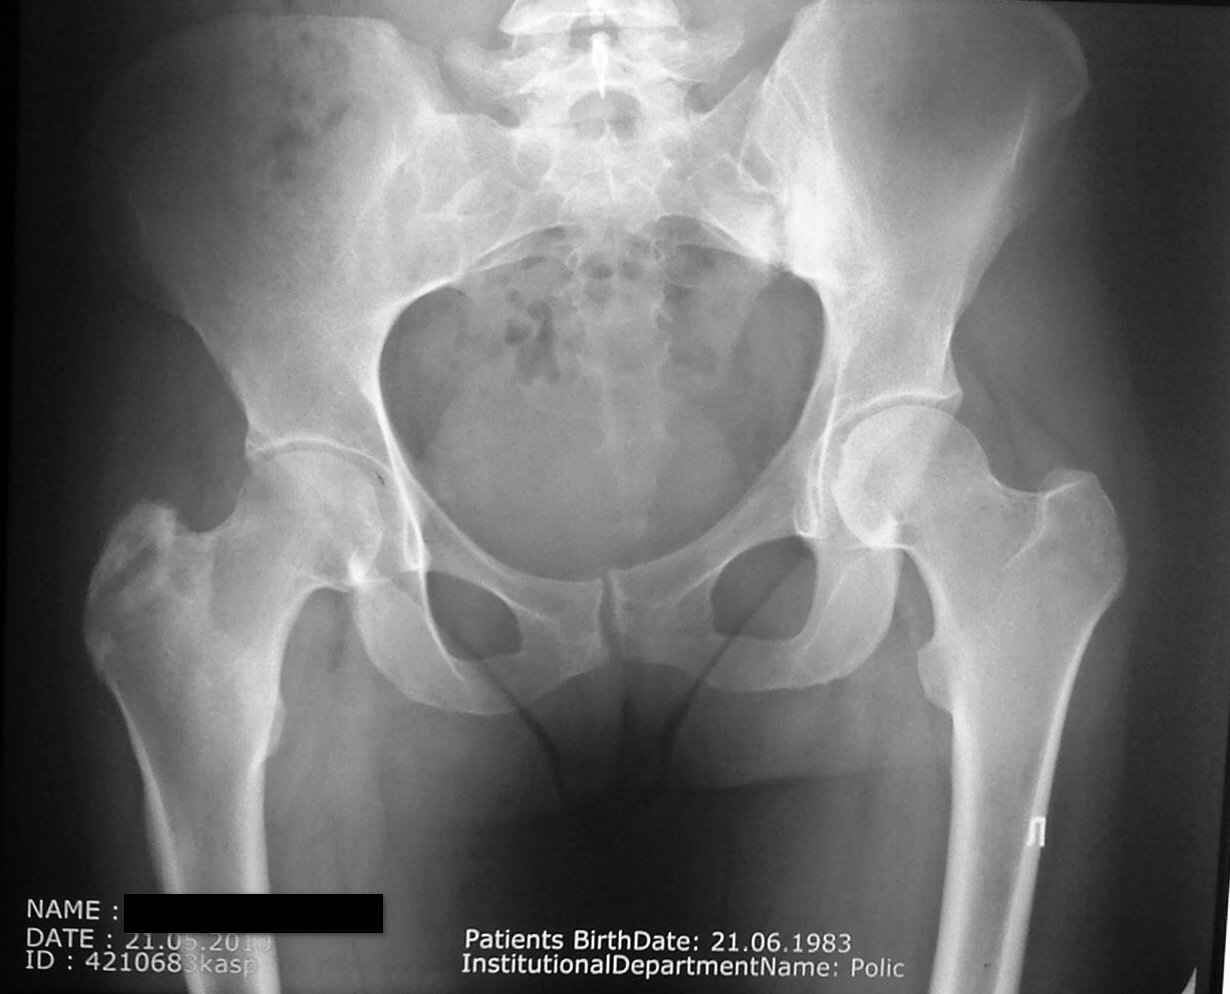

Пациентку беспокоит правый тазобедренный сустав в области вертела (именно там где имеются рентгенологические проявления . Сегодня мне были доставлены выполненное ей ранее РКТ правого коленного сустава(имеются выраженные изменения (лизис мыщелка бедра и дополнительное образование в межмыщелковом возвышении) . В биохимических анализах по ревматоидной программе изменений нет. В ОАК повышена СОЭ (29).

а мне кажется что есть изменения в большом трохантере правого бедра , смешанного характера(лизис склероз) стерты границы латерального кортекса и мягкие ткани не так четко видны как справа .. МРТ , костное сканирование , если что то есть - костная биопсия с бактериологическим исследованием ...

В верхней части диафиза выраженная периостальная реакция, над черной полосой закрывающей имя пациентки. Наверное туберкулез. Нужна биопсия и посев.

Уважаемый Олег! У больной, вероятней всего, имеется туберкулезный трохантерит справа (незначительные боли, ограничение функции тазобедренного сустава, на Р-грамме - остеопороз!!!, деструкция б.вертела, уплотнение мягких тканей. Больной показана операция - некрэктомия очага деструкции и пластика аутокостью. Бак. и гистологическое исследование операционного материала верифицирует патологический процесс. Кстати, замечу ответственно уважаемому ортопедическому сообществу, положительные результаты посева на микобактерию туберкулеза при активных процессах составляют всего 20-25%, так что отрицательный посев не означает исключение туберкулезного процесса! Желаю успехов!

Такое ощущение, что имеется анкилоз в правом крестцово-подвздошном сочленении справа. Может в какой-то степени и это причина боли!